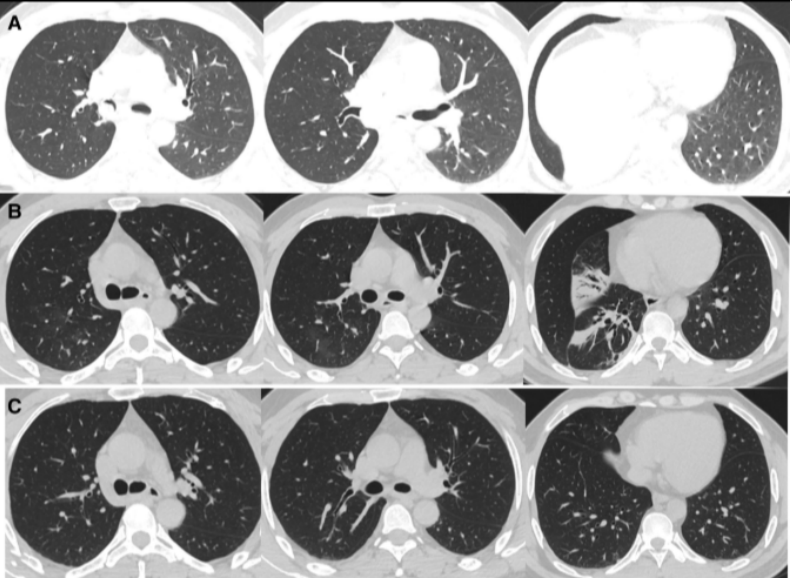

支气管镜在肺真菌病治疗中的应用主要有:①通畅气道:清除气道潴留物,解除机械阻塞。②冲洗引流:脓腔冲洗引流;液性病灶穿刺引流;炎症部位支气管冲洗;导管冲洗;穿刺引流。③局部用药:支气管冲洗、留置导管注药、药物缓释系统置入。病例:一名45岁男性因咳嗽、咳黄痰、呼吸困难持续5个月入院,患者胸部CT提示肿块引起的阻塞性肺不张(图3),但初步病理活检并未明确支持肿瘤诊断。这种不确定性可能与浅表取样有关,但不能完全排除肿瘤病变,使用硬质支气管镜检查缓解气道阻塞。术中见气道内白色肿块,该肿块松散地附着在支气管壁上(图4),镊子取出肿块时出血极少。肿块的组织学检查显示慢性化脓性炎症和肉芽肿形成、提示新型隐球菌感染。通过宏基因组二代测序证实了BALF中新生梭菌的存在。同时,血清隐球菌荚膜抗原检测结果呈阳性,氟康唑抗感染后痊愈。注:A:右主支气管和右中支气管有肿块,右下叶不张;B:右主支气管肿块消失,肺复张;C:右主支气管肿块完全消失和完全肺复张。图源:Medicine (Baltimore), 2024, 103(12):e37455.注:A:硬质支气管镜检查前软性支气管镜检查,显示右侧主支气管有肿块,导致闭塞;B:硬质支气管镜检查3天后软性支气管镜检查,证明成功从右侧主支气管中切除肿块。图源:Medicine (Baltimore), 2024, 103(12):e37455.隐球菌病胸部CT大部分表现为结节影,部分可有实变和坏死。支气管内隐球菌病导致的严重气道阻塞病例罕见,我们认为选择早期呼吸干预是一种理性的选择。首先,近一半的阻塞性支气管内隐球菌病患者对抗真菌药物反应不佳。其次,长期肺不张对肺复张构成挑战,可能导致永久性肺塌陷和肺功能受损,甚至最终导致肺实质感染和纤维化。软性支气管镜检查有助于区分内在性梗阻和外在压迫性,而硬质支气管镜检查可以更好地了解内在性梗阻性病变的性质,并提供一种气管内治疗手段。毛霉菌极易堵塞局部血管和支气管,病灶药物浓度低,单纯的全身药物治疗效果并不理想。近年来的研究发现两性霉素B局部给药,在抗真菌治疗方面会起到一定的辅助作用,包括雾化吸入、鞘内注射等,经支气管镜应用两性霉素B局部灌注对肺毛霉病可取得良好的效果。对于支气管被毛霉的菌丝体阻塞的患者,采用积极的介入治疗也可取得一定的效果,但应小心谨慎,防止出现大出血。各种介入治疗方法,包括两性霉素B局部灌注、冷冻治疗等,获得了不错的疗效。肺毛霉病的介入治疗必须具备全身麻醉、气管插管、预置球囊及有经验的呼吸内镜介入团队等。冷冻治疗建议在全麻气管插管方式下实施,出血风险高的患者还需要预置止血球囊。研究报道,10例肺毛霉病介入治疗患者均临床治愈,死亡0例。10例患者中应用冷冻探头冻取病灶8例,活检钳钳除病灶7例,套器套治疗2例,异物钳钳取病灶2例。介入和治疗经支气管镜直接局部灌注同步进行,1次/周,共1~6次。冷冻治疗的过程中3例患者预置球囊防止支气管内出血。10例患者中4级出血1例,3级出血2例,2级出血4例,3例患者无出血。支气管内出血均在5~10 min停止,术后少量痰中带血3~4天,术后气胸0例。牟向东教授团队在应用全身+局部治疗肺毛霉病的同时联合气管镜下介入技术清除阻塞气道和血管脓栓,并且在导航和超声定位下局部精准灌注两性霉素B,提高了肺组织内的药物浓度,降低了全身用药带来不良反应的概率,获得了显著的临床疗效,灌注后患者亦无明显不良反应(图5-图8)。注:右肺中叶和右肺下叶内基底段可见多发斑片影和片状肺内渗出实变影(箭头所示)。图源:https://www.btch.edu.cn/tszl/zbzx/fzjbzzzx/zb15blfx/91912.htm注:病理显示坏死组织内大量毛霉菌丝,并可见菌丝侵袭血管。